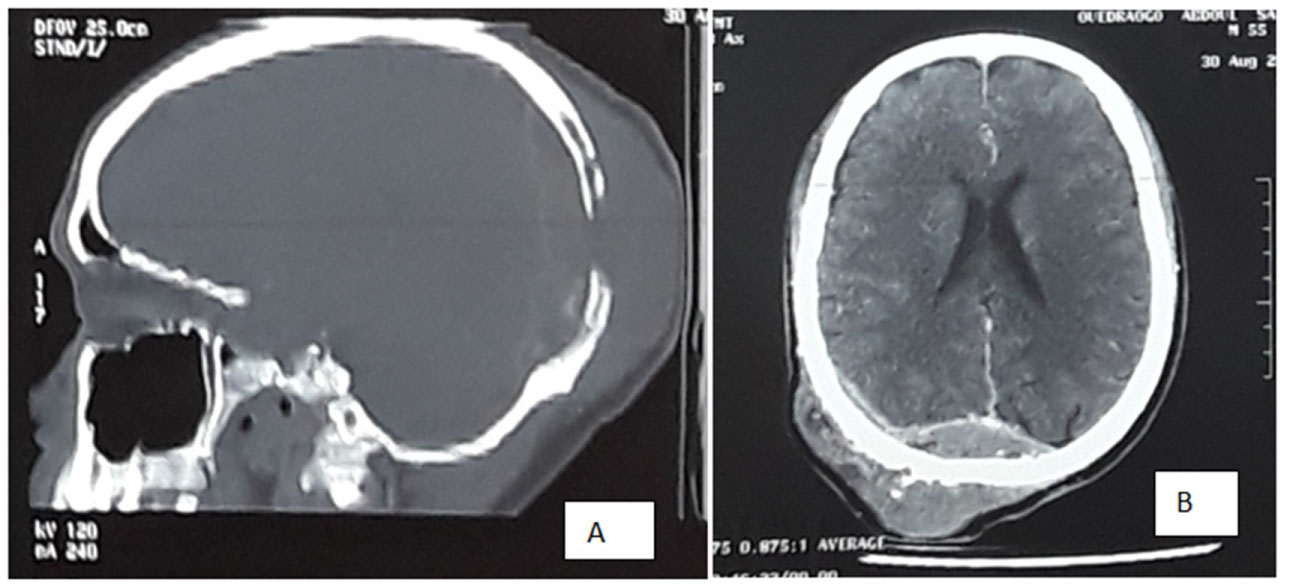

Mr. B.C, is a 66-years-old man who presented to Neurosurgery Department with swelling in the left parietal region. Subsequent evaluation revealed high PSA level of 9,202 ng/ml which warranted referral to urology unit. The swelling noticed about a year prior to presentation. It was painless and slowly increasing in size. There was no neurological or lower urinary tract symptom (LUTS). Physical examination revealed a left firm, non-tender parietal mass. The scalp and hair appears normal. Digital rectal examination revealed enlarged, hard and nodular prostate. Renal function was normal. Prostate biopsy showed adenocarcinoma, Gleason score 6 (3 + 3). Computed Tomography (CT) of the skull showed a left well-circumscribed parietal mass with bony exostosis inside and outside the skull. The overlying and underlying structures were normal (Figure 1). Bone scintigraphy showed areas of high radioactive absorption at the level of the parietal mass, as well as the left humeral head and the ribs. The patient underwent androgen privation therapy using Cyproterone 300 mg/day because he cannot afford more appropriate treatment (LHRH analog, Abiraterone, chemotherapy). He had regular follow up, the lowest PSA recorded was 3 ng/ml after 8 months of treatment. The parietal swelling has reduced in size. At 18th month of treatment, the PSA level rose to 102 ng/ml and the serum Testosterone was 0.1 ng/ml. The general condition of the patient gradually deteriorated and he died few months later.

Figure 1: Brain CT showing osteoblastic mass of the cranial vault A) Soft tissue window; B) Reconstructed image. View Figure 1

S.A is a 65-years-old man who was also referred from Neurosurgery Department where he presented with right temporal swelling of 9 months duration. The swelling was painless but there was associated right ear hearing impairment. PSA level was found to be 6,909 ng/ml during the course of his evaluation. There was nocturia of 4 to 5 times per night, no other LUT or urological symptoms. Physical examination revealed a firm and non-tender mass involving the whole right temporal region. The overlying skin appears normal. On digital rectal examination, the prostate was small, hard and irregular. Ear-nose-throat (ENT) examination revealed right conductive deafness due to temporal bone deformity and partial obstruction of the external auditory canal. The histological examination of the prostate biopsy samples revealed adenocarcinoma. Computer tomography of the brain showed thickening of the right temporal bone with prominent bony exostosis compressing on the brain (Figure 2). Patient had bilateral orchiectomy. Follow up at 2, 15 and 24 months revealed PSA levels of 295 ng/ml, 268 ng/ml and 100 ng/ml respectively with a significant improvement of clinical symptoms and signs, as well as a reduction in size of the temporal swelling.

Figure 2: Brain CT showing right temporal bone mass compressing on the brain. A) Bone window showing an osteoblastic lesion of the right temporal bone; B) Soft tissue window showing a swelling of the extracranial tissues and brain compression. View Figure 2